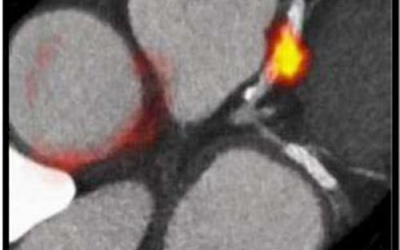

Ngày 18/11, tại Hà Nội, Bệnh viện (BV) Phổi Trung ương khai trương và đưa vào hoạt động Trung tâm xạ trị ung thư phổi công nghệ xạ trị gia tốc tuyến tính.